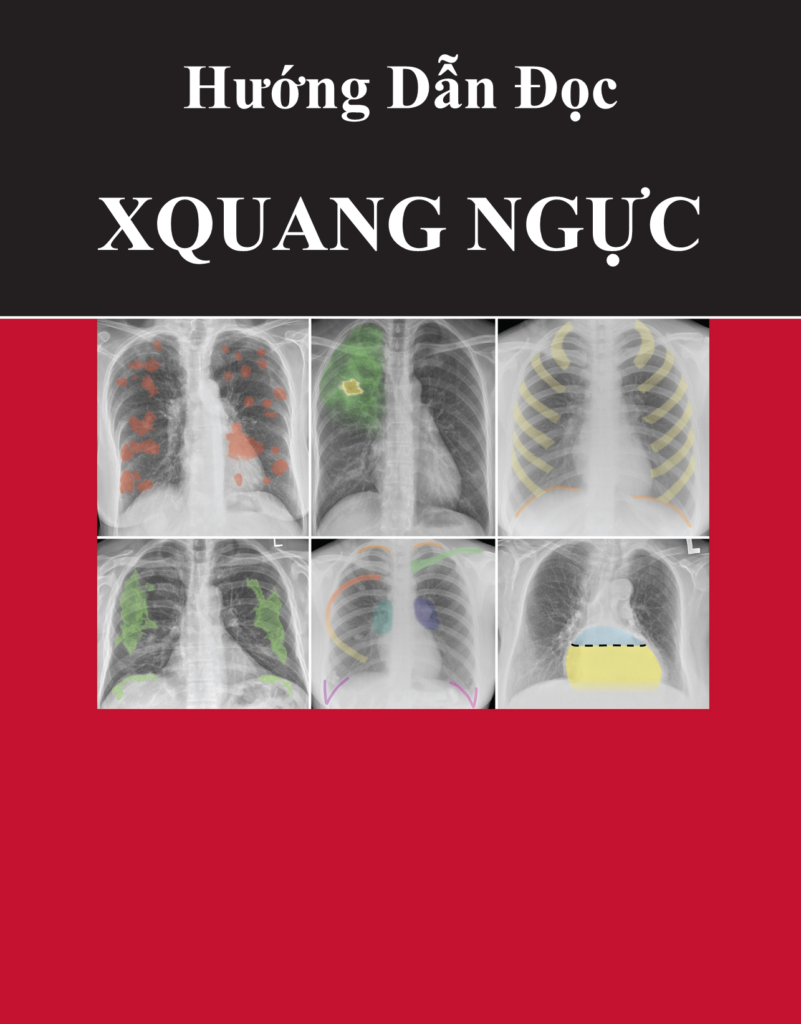

Hôm nay, Trang vừa sưu tầm được một tài liệu hay về chẩn đoán hình ảnh và X-quang nên muốn chia sẻ đến các bạn để chúng ta cùng nhau tham khảo nhé. Một cuốn sách được dịch thuật từ : “Chest Xrays for Medical Students” của bác sĩ Lê Trọng Nhân chia sẻ. Cuốn […]